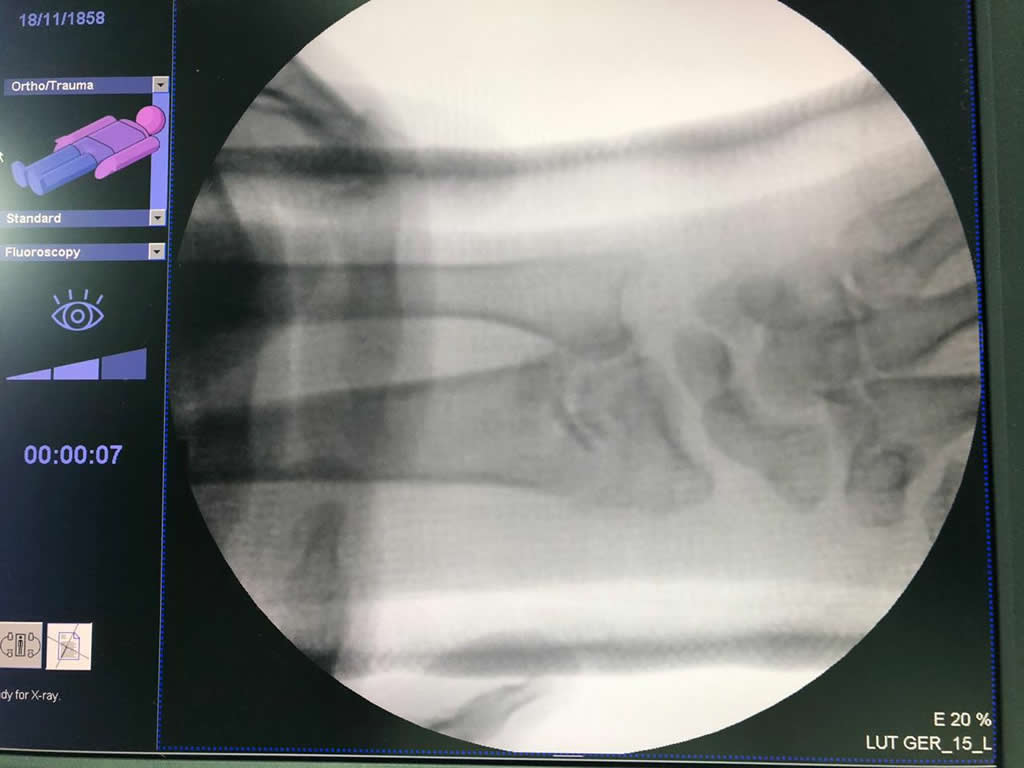

Cirugías de Codos - Cirugías de Muñecas y Manos

Los procedimientos más comunes en cirugía de la mano son aquellos destinados a reparar traumatismos, incluyendo lesiones de tendones, nervios, vasos sanguíneos, y articulaciones; huesos fracturados; y quemaduras, cortes, y otros daños de la piel.